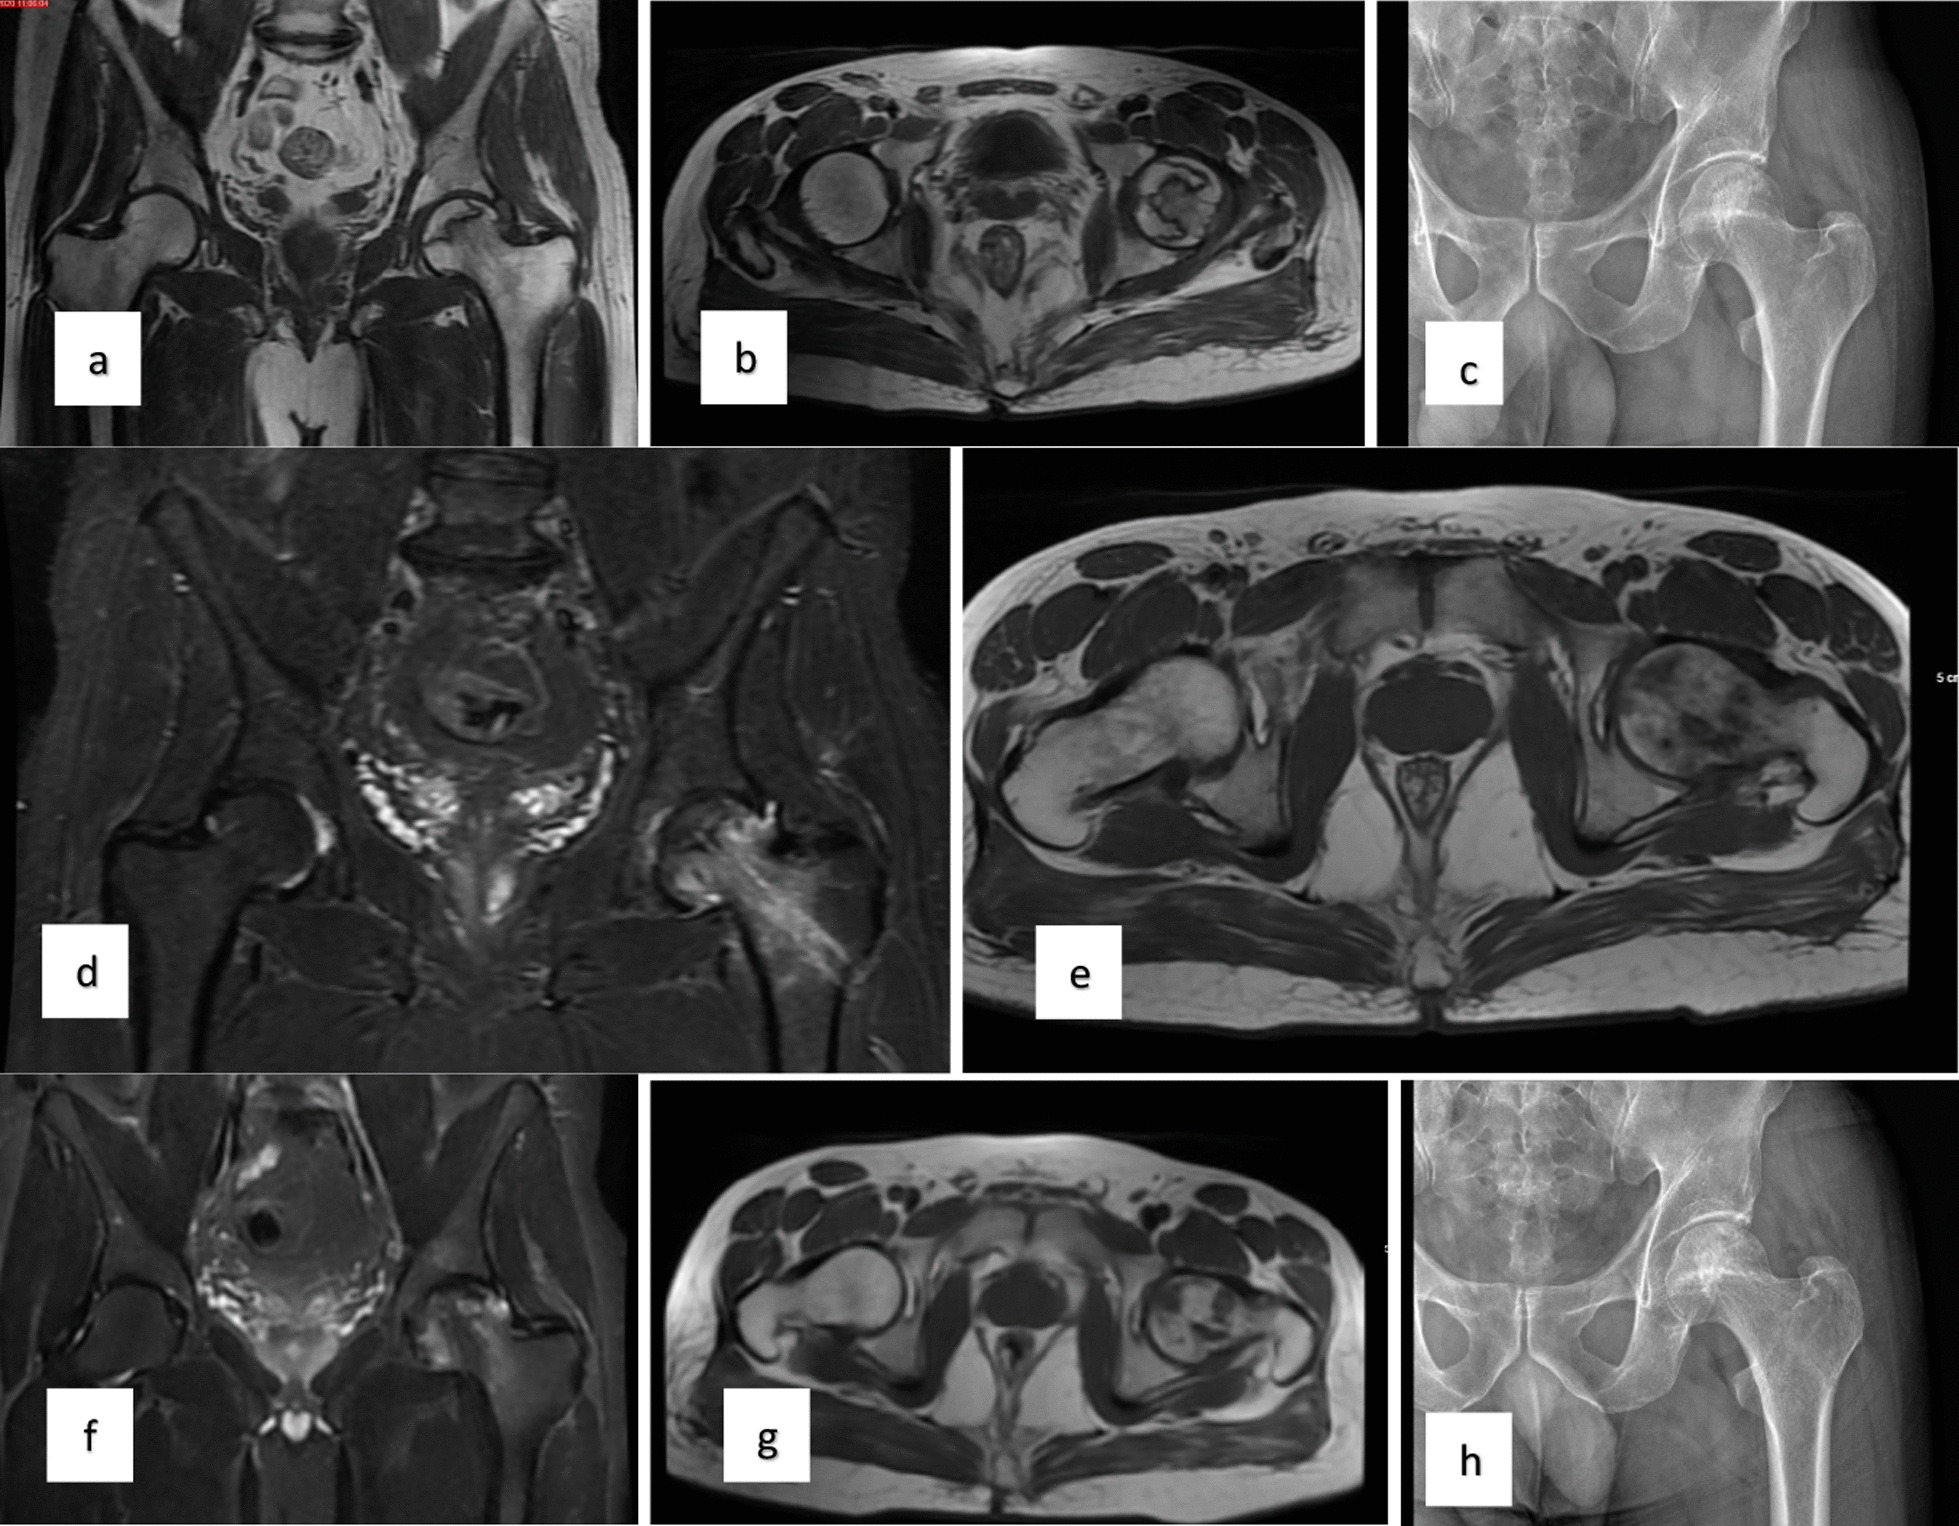

对患者的术前、3个月、6个月、1年和2年随访进行评估(图1)。

当评估第1组和第2组的VAS评分时,得出结论:基线和第3个月的VAS评分相似;6、12、24个月时差异有统计学意义,第2组VAS评分明显较低。比较各组患者的HHS时得出的结论是,基线评分相似,第2组在第24个月时有显着改善。此外,两组治疗前后的HHS均显着改善。第1组和第2组患者VAS评分变化见表1,HHS评分见表2(图2)。